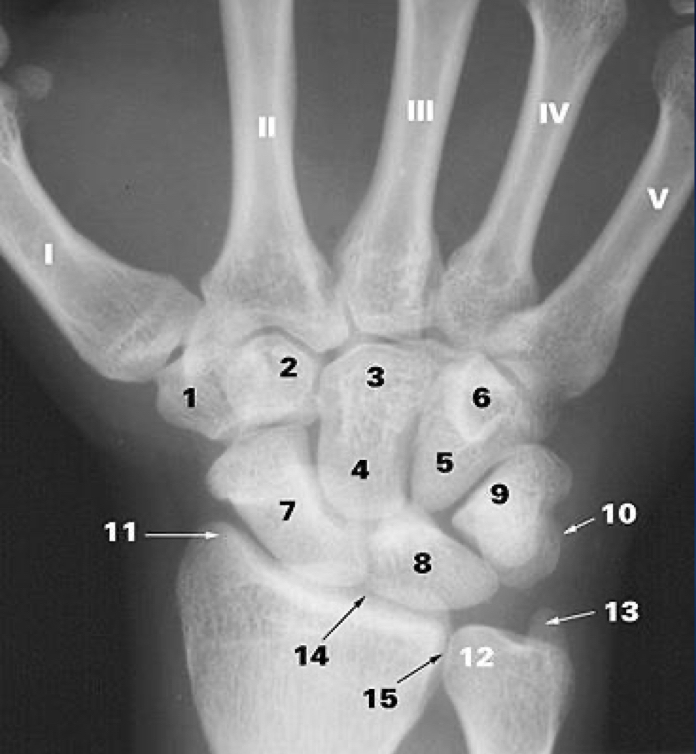

1

What is 1?

trapezium b.

2

What is 2?

trapezoid b.

3

What is 3?

capitate b.

4

What is 5?

hamate b.

5

What is 6?

hook of hamate

6

What is 7?

scaphoid b.

7

What is 8?

lunate b.

8

What is 9?

triquetrum b.

9

What is 10?

pisiform

10

What is 11?

styloid process of the radius

11

What is 12?

head of the ulna

12

What is 13?

styloid process of ulna